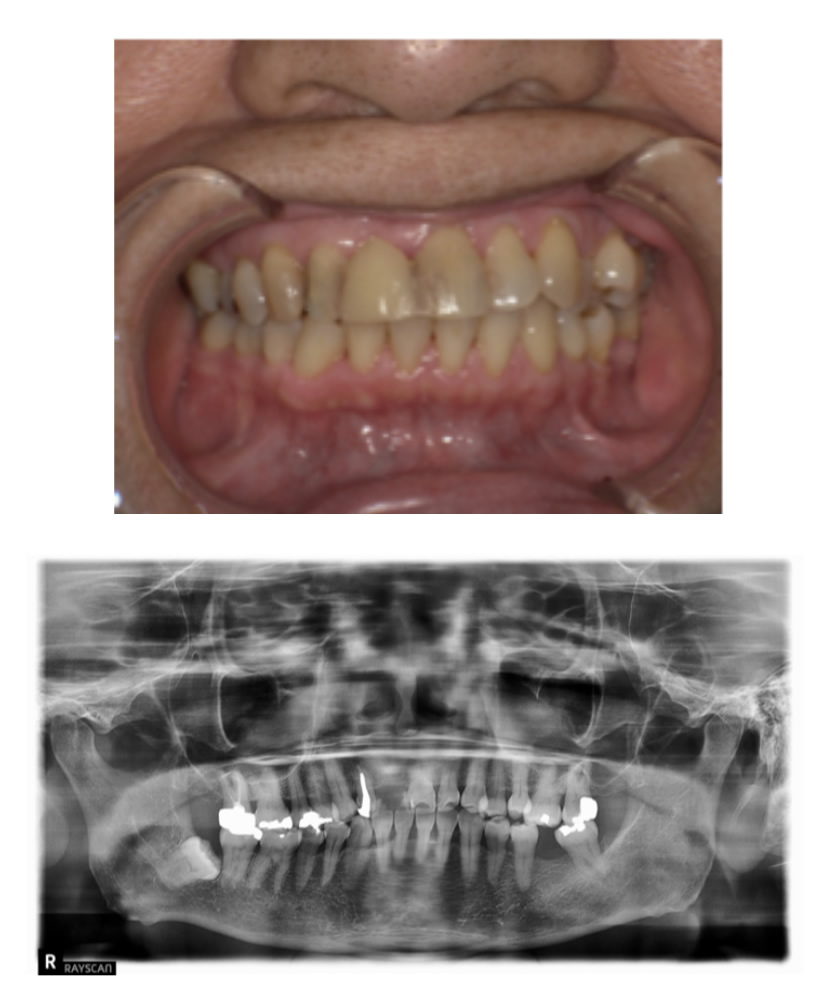

06 症例

歯が割れて痛いのでインプラント希望

Before

After

| 治療内容 | 歯が割れていて咬むと痛いのでインプラント希望 |

| 患者さま | 60代女性 |

| 主訴 | 咬むと痛いのでインプラントにしたい |

| 治療期間(目安) | 3ヶ月 |

| 治療費(税込:目安) | ¥518,100 |

| リスク | 術後に多少の痛みや腫れが出ることがある。歯肉退縮がおきると、歯と歯肉の間に隙間が生じることがあります。 |